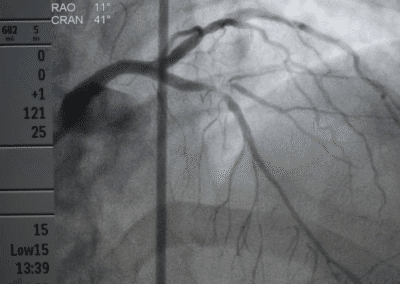

- Angioplastica: Un intervento minimamente invasivo per dilatare le arterie ristrette, ripristinando il flusso sanguigno.